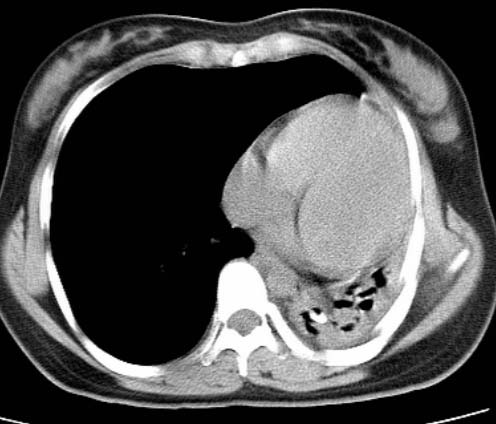

女  20岁。一月前咳血,诊“肺结核”抗痨治疗一月后,咳血停止,现复查。病人精神好。前后ct片对比未见明显变化。既往体检“正常”

1)考虑左肺结核并肺不张、支气管扩张。2)纵隔疝。

以前体检正常只能考虑左肺结核并肺不张、支气管扩张。2)纵隔疝。

考虑左肺结核,左肺毁损,纵膈左偏,既往体检正常不可靠,tb一个月也不会这个样子的,有钙化,应该病程较长,冰冻三尺非一日之寒!

左肺发育不全。

考虑左肺结核,左肺毁损,纵膈左偏,既往体检正常不可靠,tb一个月也不会这个样子的,有钙化,应该病程较长,冰冻三尺非一日之寒

结核,左肺毁损。